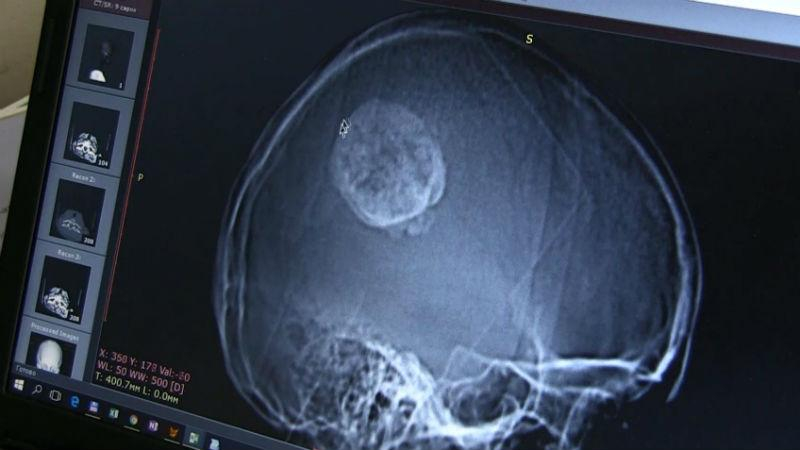

На снимке головы 32-летней пациентки перед вмешательством видно большую опухоль и что-то похожее на крючок, который вцепился в мозг. В этой части к нему не подобраться.